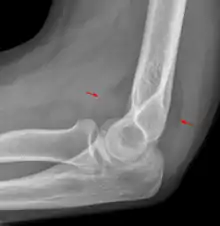

Anterior sail signs as well as posterior fat pad in a child with a supracondylar fracture.